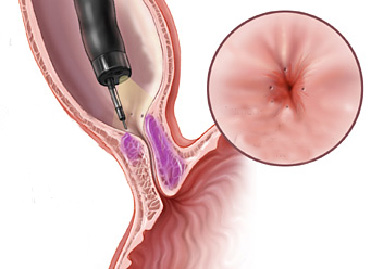

Mucosectomia é o procedimento realizado quando há necessidade de retirada de lesões maiores do trato gastrointestinal.

O exame de Mucosectomia é realizado através de injeção de liquido embaixo da lesão, através de uma agulha específica. Com isso a lesão se destaca das camadas mais profundas do intestino, diminuindo o risco de perfuração.

A retirada da lesão é feita com uma alça de polipectomia e o material é encaminhado para estudo anatomopatológico (no microscópio) da mesma forma que ocorre nas biópsias.

Mucosectomia

Para diminuir este risco, injeta-se com um uma agulha uma solução abaixo do pólipo para que ele levante e fique mais longe da parede do órgão. Após isto passa-se a alça diatérmica e realiza-se o

procedimento de polipectomia.